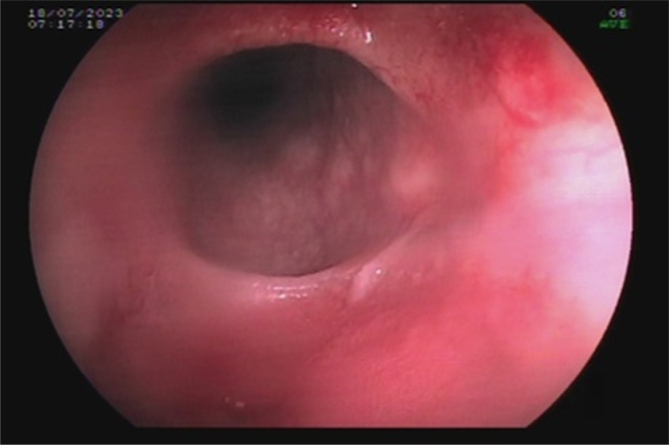

HETEROTOPIC GASTRIC MUCOSA OF THE ESOPHAGUS AS A POTENTIAL CAUSE OF PEPTIC STENOSIS AFTER ROUX-EN-Y GASTRIC BYPASS.

{"title":"HETEROTOPIC GASTRIC MUCOSA OF THE ESOPHAGUS AS A POTENTIAL CAUSE OF PEPTIC STENOSIS AFTER ROUX-EN-Y GASTRIC BYPASS.","authors":"João Victor Vecchi Ferri, Wagner Herbert Sobottka, José Alfredo Sadowski, Gustavo Rodrigues Alves Castro, Vitor Mamoru Haida, Marcela Scardua Cocicov, João Caetano Dallegrave Marchesini","doi":"10.1590/0102-6720202400055e1849","DOIUrl":null,"url":null,"abstract":"","PeriodicalId":72298,"journal":{"name":"Arquivos brasileiros de cirurgia digestiva : ABCD = Brazilian archives of digestive surgery","volume":"37 ","pages":"e1849"},"PeriodicalIF":1.8000,"publicationDate":"2025-01-20","publicationTypes":"Journal Article","fieldsOfStudy":null,"isOpenAccess":false,"openAccessPdf":"https://www.ncbi.nlm.nih.gov/pmc/articles/PMC11745473/pdf/","citationCount":"0","resultStr":null,"platform":"Semanticscholar","paperid":null,"PeriodicalName":"Arquivos brasileiros de cirurgia digestiva : ABCD = Brazilian archives of digestive surgery","FirstCategoryId":"1085","ListUrlMain":"https://doi.org/10.1590/0102-6720202400055e1849","RegionNum":0,"RegionCategory":null,"ArticlePicture":[],"TitleCN":null,"AbstractTextCN":null,"PMCID":null,"EPubDate":"2025/1/1 0:00:00","PubModel":"eCollection","JCR":"","JCRName":"","Score":null,"Total":0}